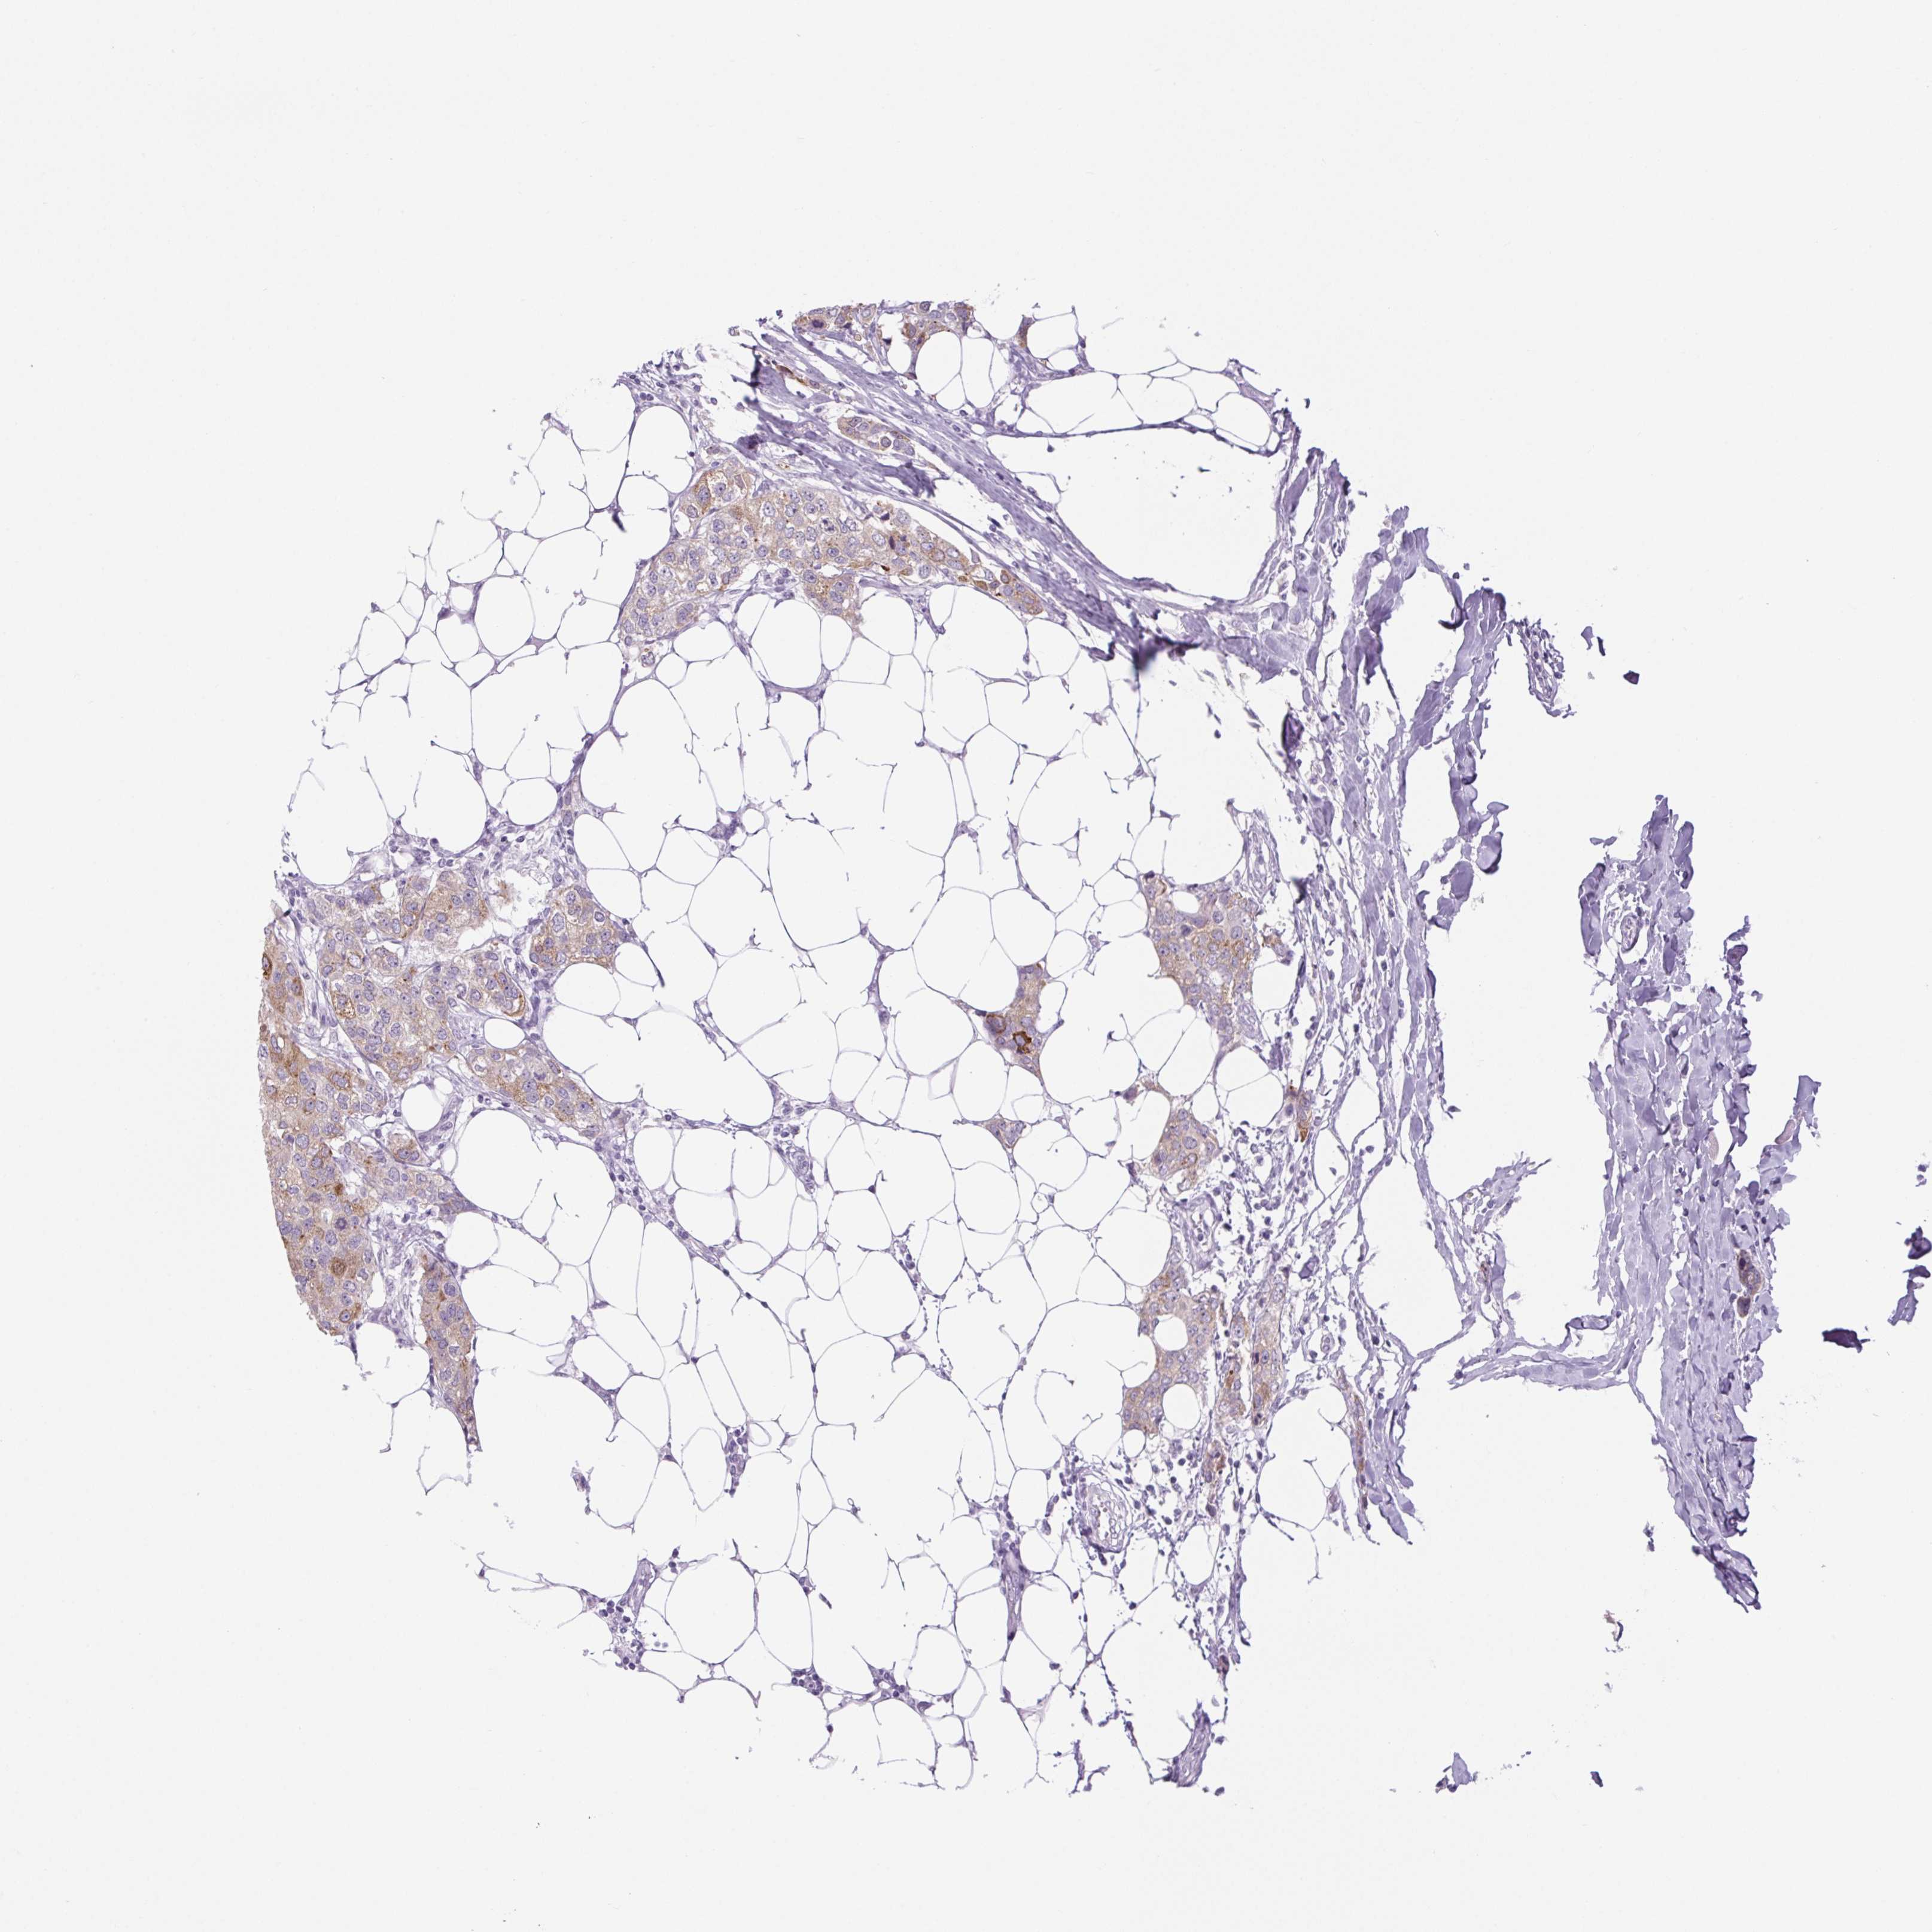

CANCER BREAST CANCER Show tissue menu

BRCA TCGA BRCA VALIDATION PROTEIN EXPRESSION